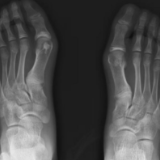

什么是踇外翻(HAV)?

踇外翻俗称“大脚骨”,是一种常见的足趾畸形,是指大脚趾在第一跖趾关节处发生向外侧偏斜移位的现象,表现为该脚趾相对于其他脚趾明显向外翻转;较严重的情况下,踇趾会与第二趾上下重叠,即位于第二趾的上面或下面。此症状多见于中老年妇女群体,并具有一定的遗传倾向。此外,长时间穿着不合适的鞋子也可能导致踇外翻的发生。

通常情况下,患有拇外翻的个体能够直接观察到踇趾的外翻畸形,从而实现初步诊断。然而,标准的X线检查对于评估拇外翻畸形程度具有更为显著的优势。

踇外翻的四期发展阶段

第一阶段:较轻微,大踇指外翻10度左右,主要表现为踇趾内侧轻微隆起。

第二阶段:中度,大踇指外翻10-20度左右,主要表现为第一跖骨头内收,踇指外展对第二跖骨造成压力,第一趾跖关节内侧及踇指内侧会形成胼胝,加剧外展。此外,软组织(如踇长伸肌)会收紧,将拇指向外侧(即第二跖骨)的方向牵拉,加剧踇趾外展。

第三阶段:较严重,大踇指外翻20-40度左右,脚趾有重叠现象,横弓塌陷,出现鸡眼、扁平足、后跟疼痛、双足受力不均等症状,严重影响站立和行走能力。

第四阶段:重度,因第一、第二阶段未对HAV进行矫形治疗,踇外翻进一步发展,进入第四阶段。主要表现为踇趾和第二跖骨上重叠或下重叠,即踇趾高于或低于第二跖骨。脚趾不受力,足弓塌陷,难以行走,双下肢生物力线改变,引起膝关节炎和腰酸背痛,且治疗也是非常困难,患者也极其痛苦,通常很难找到可容纳踇趾歪斜的鞋子。

注:HV表示踇趾外翻角度,IMA表示第一趾骨和第二趾骨的角度。